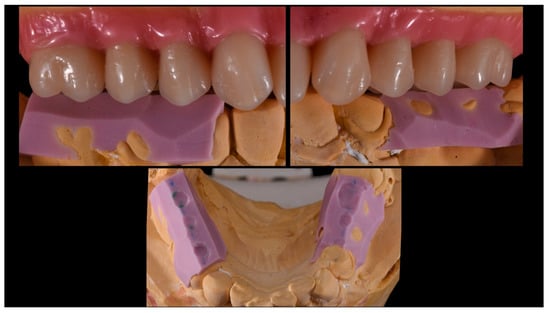

Angled Screwdriver Solutions and Low-Profile Attachments in Full Arch Rehabilitation with Divergent Implants

2. Report and Protocol